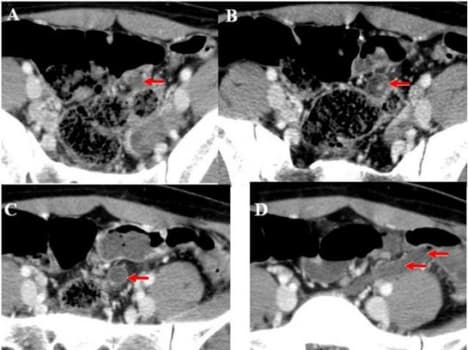

Hình ảnh CT viêm ruột thừa

Ruột thừa là một bộ phận nhỏ như ngón tay cái nằm ở bên phải của bụng. Do một nguyên nhân nào đó như: sỏi thận, dị vật… bộ phận này rất dễ bị viêm, sưng, nhiễm trùng,… Một trong những phương pháp chẩn đoán chính xác nhất căn bệnh này đó là chụp MSCT. […]